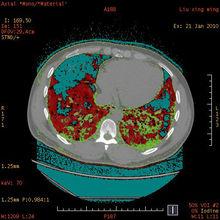

多能譜CT圖7 定量分析並顯示物質密度、CT值、有效原子序數等數據(圖像來源:陝西中醫學院附屬醫院)

把符合設定閾值範圍內的體素用顏色標示出來,即檢出並標記相似化學構成的組織(圖像來源:陝西中醫學院附屬醫院)

多能譜CT圖8 有效原子序數